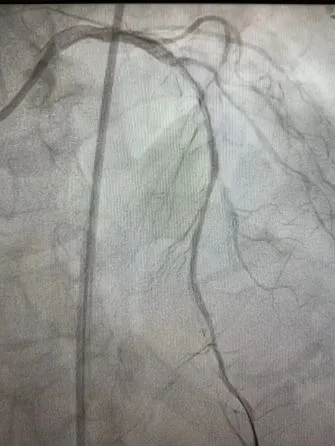

支架术后左冠状动脉开通